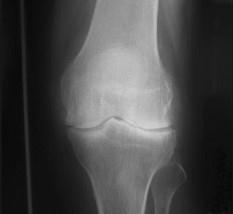

问题 女,56岁,手指关节肿胀,疼痛,僵硬,结合影像图像,选择最可能的诊断 ( )

选项 A、Reiter综合征 B、骨囊肿 C、类风湿关节炎 D、痛风性关节炎 E、关节结核

答案 C